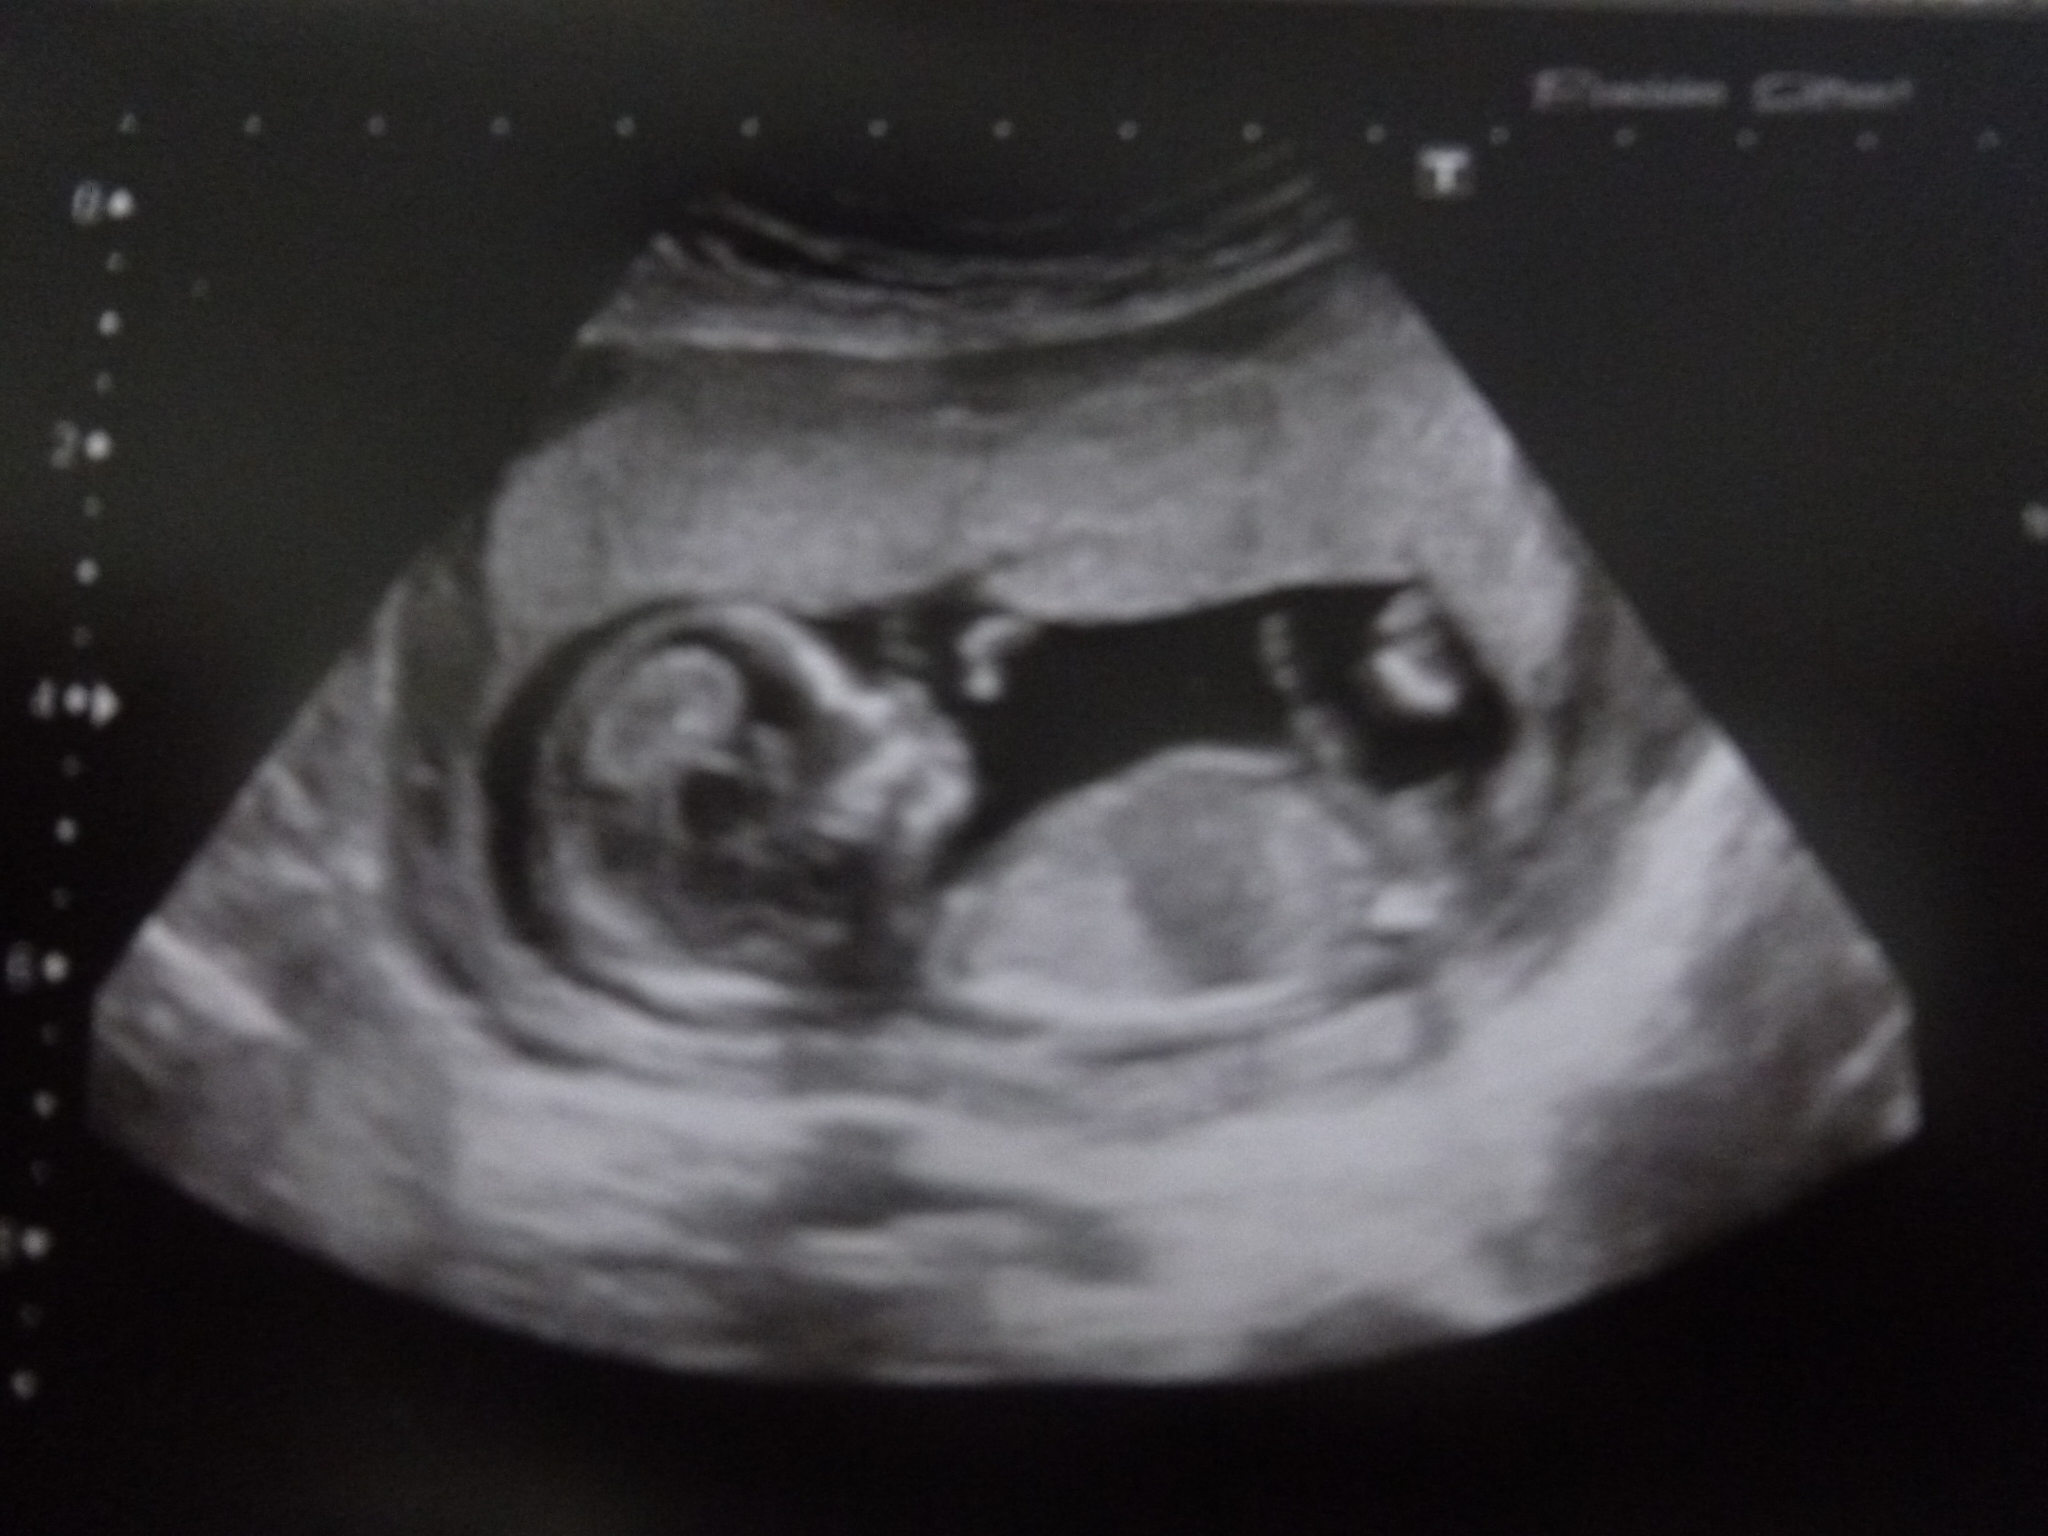

Another little lady.

Anyhow it was pretty obvious during my anomaly scan that I am having another little girl, the sonographer confirmed this. My husband seemed a little disappointed, he would have been delighted with a boy. We have not told anyone and are going to keep it quite. My eldest Dd really wanted a little brother so I do feel a little bad for her.

Attachment 6540